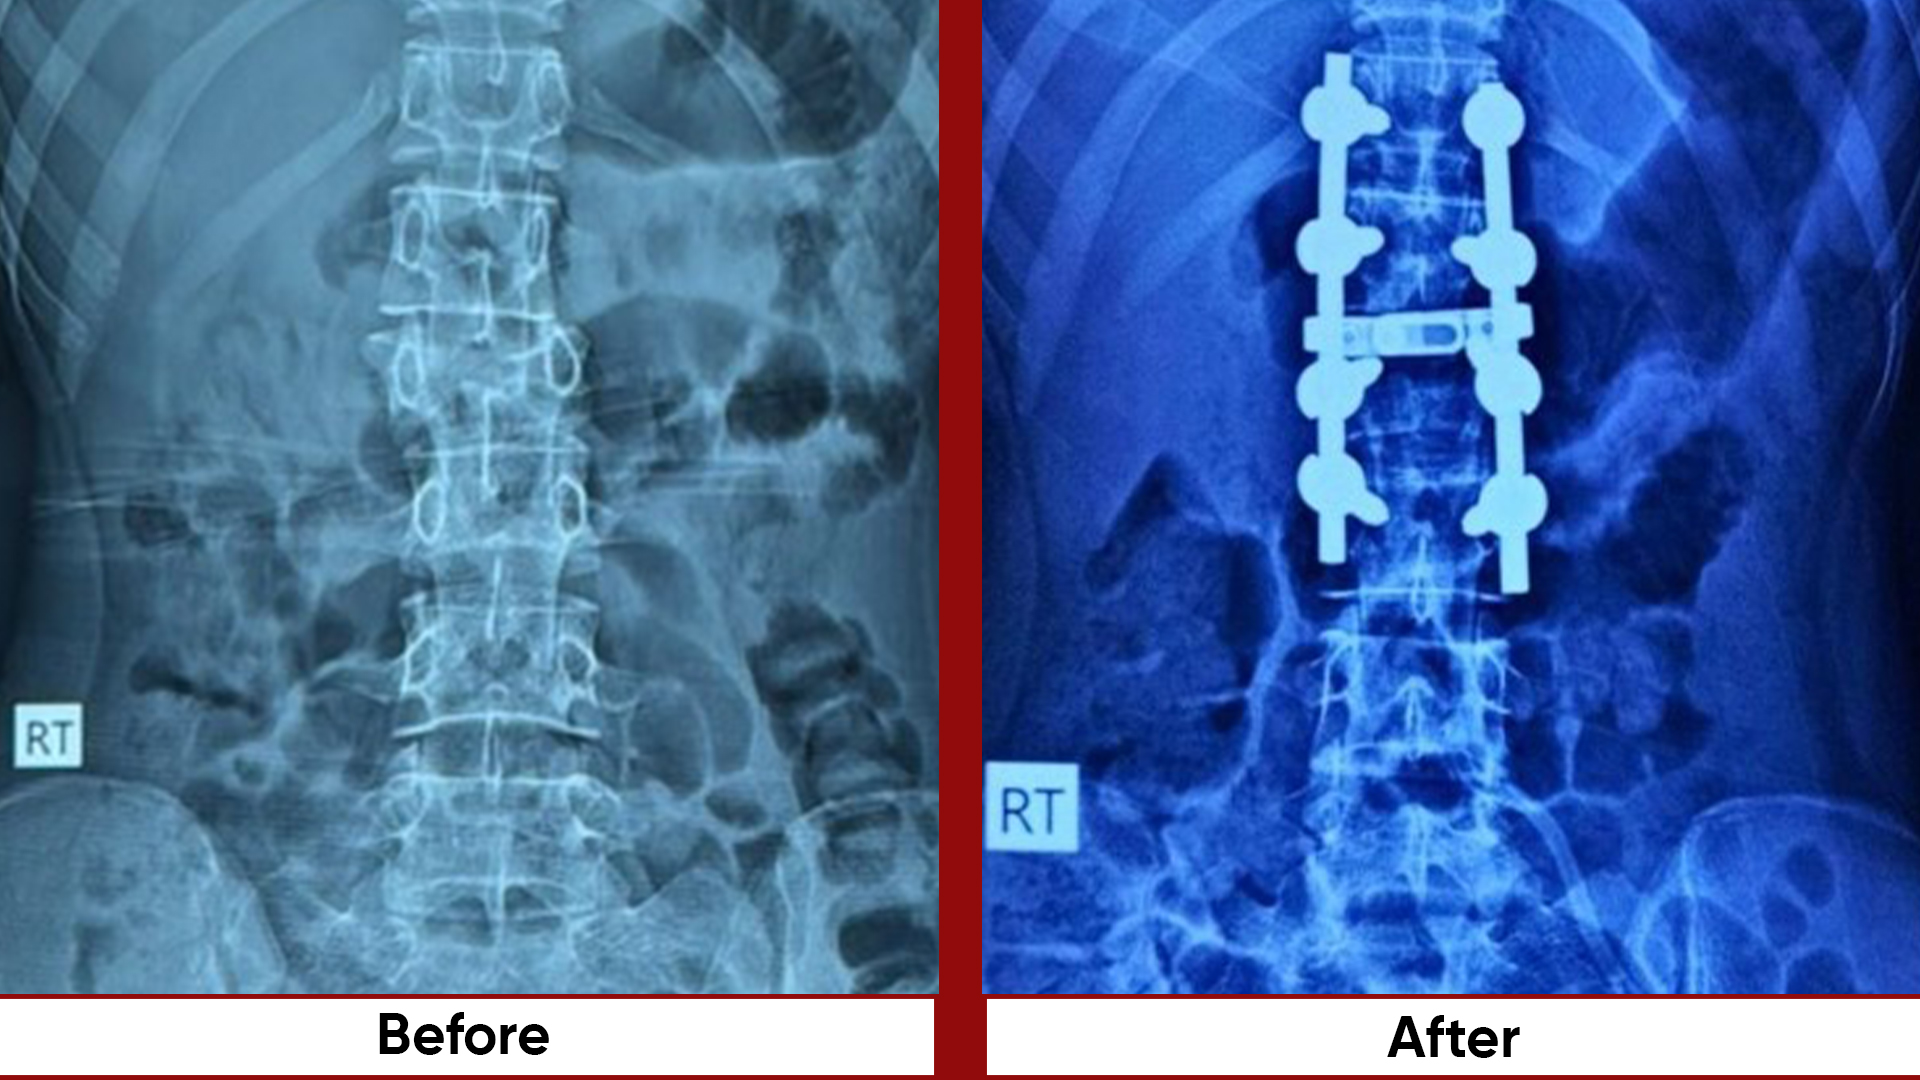

• Fracture Management (simple and complex trauma)

• Bone Tumor Management